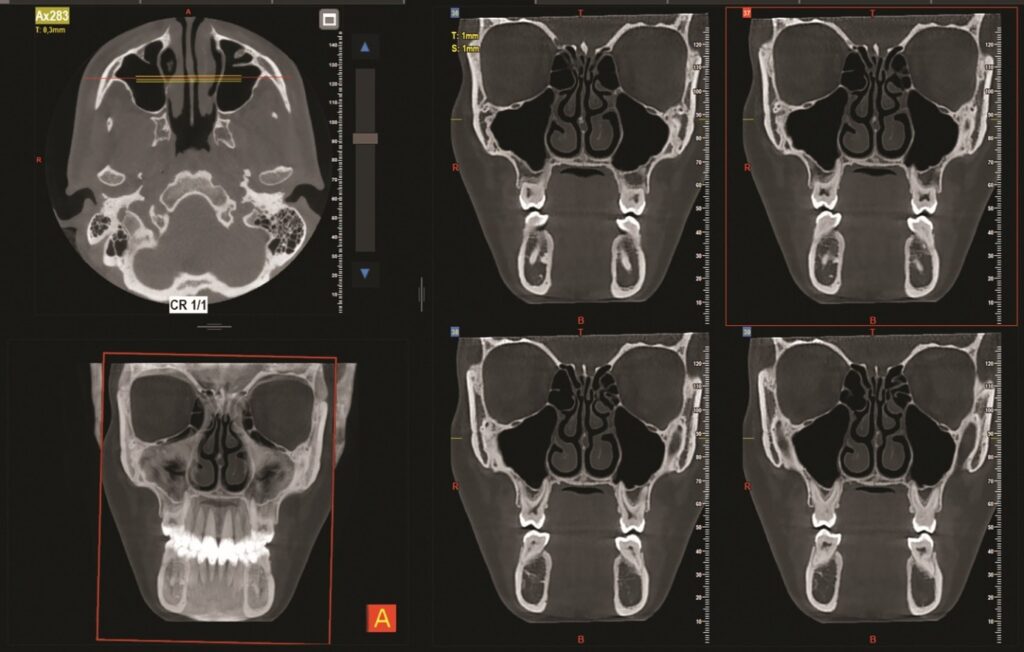

7G NewTom umožňuje zobrazenie veľmi jemných kostných štruktúr, ako sú sluchové kostičky, kostné steny prínosových dutín, vnútorné štruktúry stredného a vnútorného ucha. To je mimoriadne dôležité pri diagnostike chronických zápalov, cholesteatómov, malformácií a fraktúr.

CBCT poskytuje reálne 3D zobrazenie bez geometrického skreslenia. Lekár môže rotovať obraz v priestore, robiť presné rezy v ľubovoľnej rovine, merať vzdialenosti a objemy. To je kľúčové pri plánovaní operácií v ľubovoľnej anatomickej oblasti tela, napríklad prínosových dutín a nosových priechodov.

Diagnostika prínosových dutín — CBCT je dnes považované za zlatý štandard. Umožňuje presne odhaliť polypy, cysty, zhrubnutie sliznice a anatomické varianty, ktoré môžu spôsobovať chronické ťažkosti.